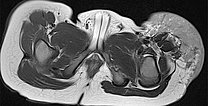

Auch in der axialen Schichtführung der MRT (T2-gewichtet, fettgesättigt) ist die Infiltration der Muskulatur durch die Raumforderung gut dargestellt. Auch Hämangiome können als vaskuläre Tumoren eine solche Infiltration aufweisen, ohne dass sie maligne sein müssen.

Die axiale T2-Wichtung ohne Fettsättigung zeigt den Tumor homogen nur gering hyperintens. Er ist zwar hyperintenser als Muskulatur, aber insgesamt deutlich weniger hyperintens als das umgebende subkutane Fettgewebe.